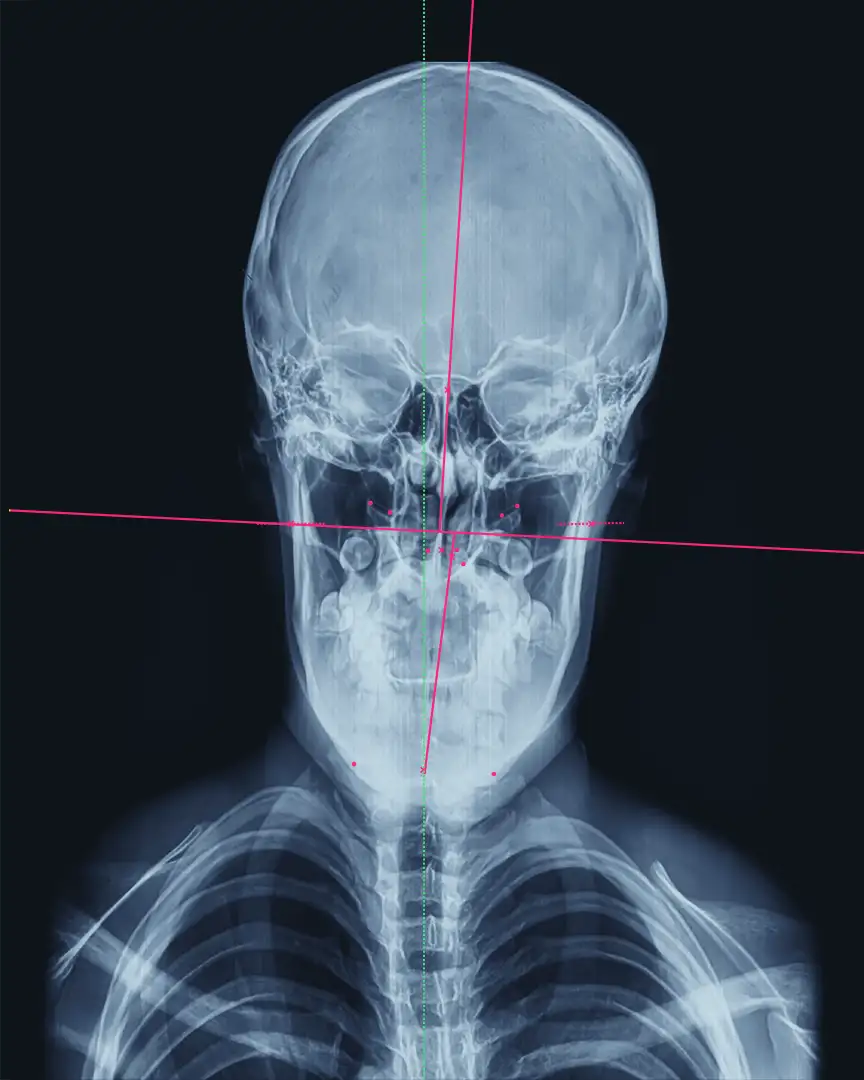

Frontal X-ray of severe misalignment of the spine

We use imaging and measurements (when needed) to understand your upper neck alignment and determine the most accurate correction for you. That means the adjustment can be lighter and more targeted.